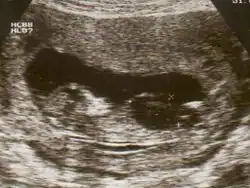

| Ultrasound of fetus with Down syndrome showing a large bladder | |

Fetal megacystis[1] is a rare disease that is identified by an abnormally large or distended bladder.

Fetal megacystis is diagnosed during pregnancy by ultrasound imaging procedures. Since it can be associated with genetic abnormalities, further ultrasounds and tests may be administered during pregnancy. It may also be diagnosed as megalocystis, and/or termed megabladder, which is the same condition.